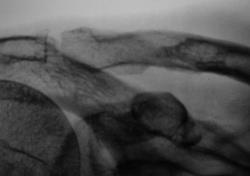

Мне и надостная часть лопатки не нравится, и ость ее как-то вогнута книзу. Вообще, если посмотреть на первый (обзорный) снимок в целом, создается впечатление об овальном объемном образовании, исходящем из мягких тканей надостной области и давящей на ключицу снизу, а на лопатку и ее ость сверху. Как вариант, какая-нибудь рабдомиосаркома.

Спасибо Андрей Юрьевич. Я понял, что наиболее правильнее считать, что надостной ямы фактически нет, она полностью разрушена, как и разрушен верхний край лопатки,  осталась одна лопаточная ость, а именно её "зависшие остатки" и инфильтративный рост распространился на ключицу.